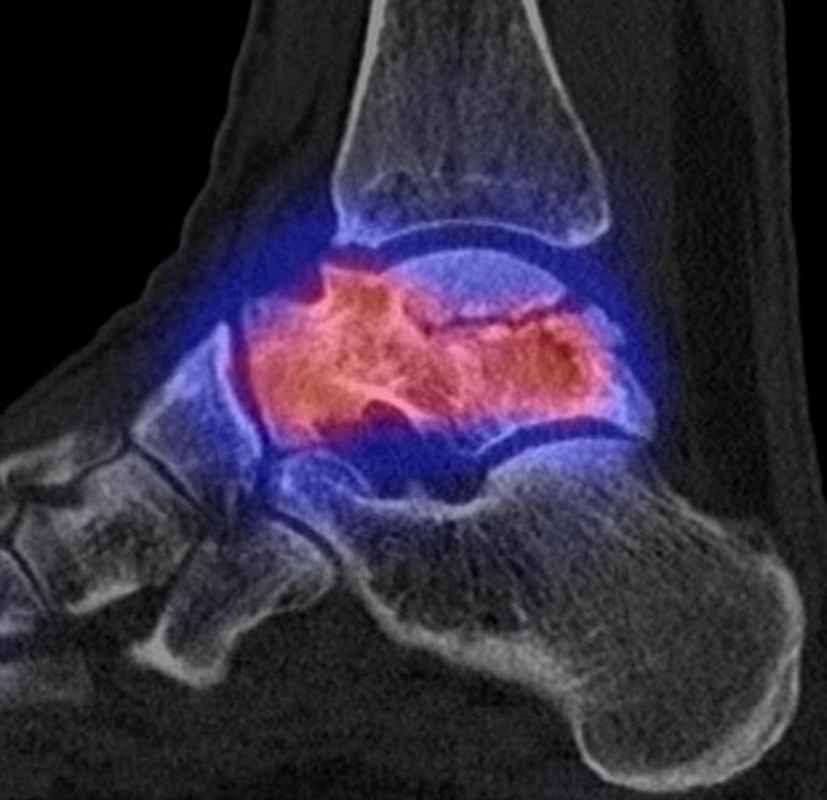

Osteonekrosen

Abbildung 9.2.a bis d: SPECT/CT zur Beurteilung der Knochen-Vitalität bei einer Talusnekrose. 5 Jahre zuvor während der Arbeit war die Patientin beim Treppensteigen umgeknickt und zog sich Außenbandrupturen zu. Nachfolgend persistierende Beschwerden mit Entwicklung einer Talusnekrose. Frage nach Vitalität und Ausdehnung der Nekrose. Deutliche bis intensive Traceranreicherung im Bereich des linken Talus. Im SPECT/CT befindet sich der Hypermetabolismus in allen Abschnitten des Talus mit relativer Aussparung eines sich demarkierenden Fragmentes lateral, was die laterale Talusschulter umfasst, die Größe beträgt transversal ca. 23 x 16 mm. In diesem Fragment relativ homogene Skelettstruktur, diese Befunde weisen auf eine trophische bzw. nekrotische Störung des Talus hin mit einem sich demarkierendem Fragment, welches die laterale Talusschulter beinhaltet.

Die Abbildung 9.3.a bis d zeigt ein weiteren Fall mit einer SPECT/CT zur Beurteilung der Knochen-Vitalität bei einer Talusnekrose. Die Bilder zeigen eine abgelaufene Nekrose mit zystischen Resorptionen des linken Talusdoms bei nachweislich erhaltener Vitalität der umgebenden Knochenabschnitte aufgrund des hier überall deutlich erhöhten Knochenmetabolismus (= inkomplette Restitutio). Aufgrund der nachweislich erhaltenen Vitalität konnte erfolgreich eine Knochen-Transplantation erfolgen.Deutlich geringer ausgeprägte nekrotische Veränderungen auch im rechten Talusdom bei hier weitgehend erhaltenen Gelenkkonturen.